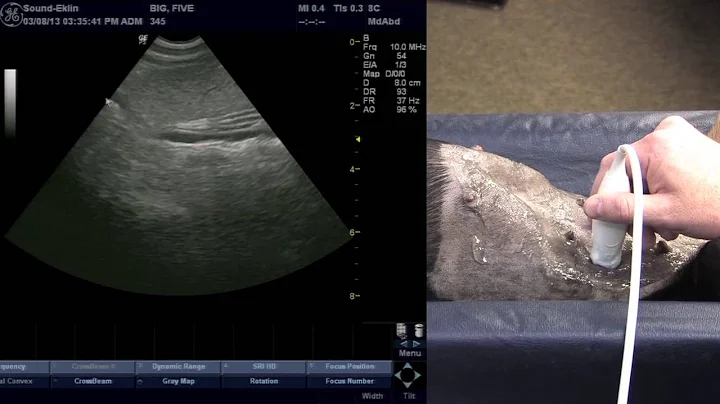

Ultrasound Of The Canine Spleen

Book a 1-on-1 Clarius demo: https://clarius.com/getdemo In this video Dr. Edwards shows patient and scanner positions for a ...